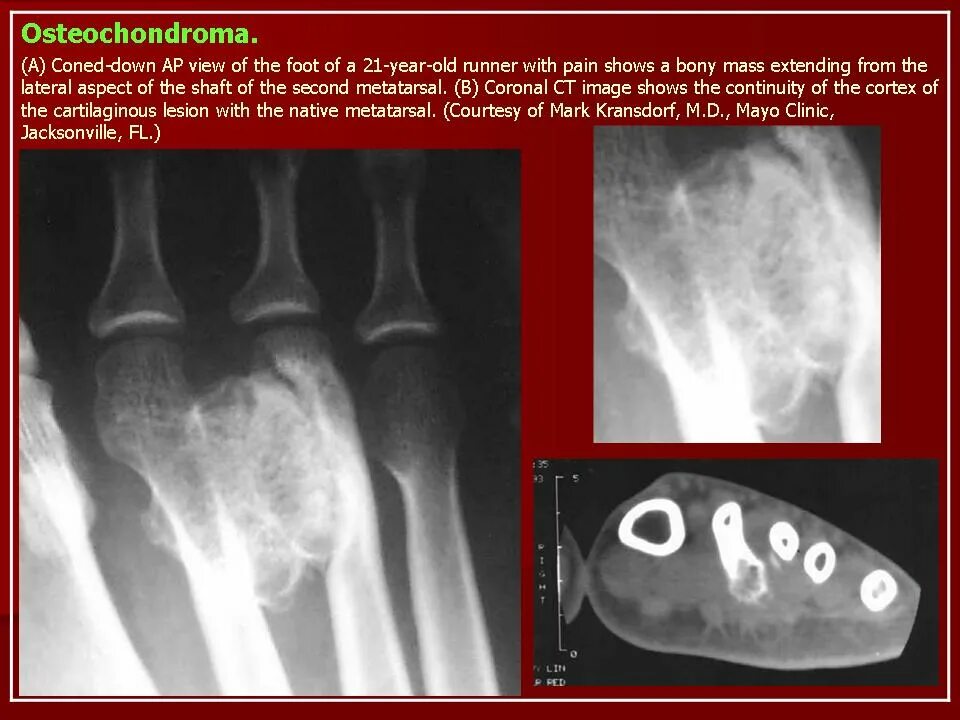

Экзостоз мкб 10